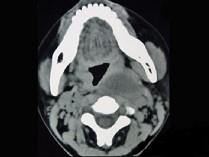

问题 女性,34岁,自诉1个月前被咽喉部被鱼刺刺伤,近半个月发热,咽喉部疼痛,CT检查如图所示,请选择正确的描述和结论 ( )

选项 A、考虑神经源性肿瘤 B、考虑血管瘤 C、肿块内密度均匀 D、考虑咽后壁脓肿 E、左侧咽后壁可见低密度肿块影

答案 CDE